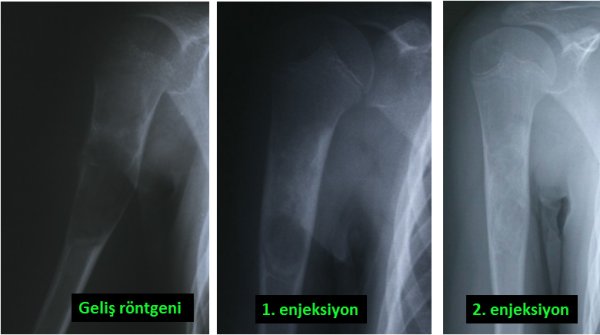

Benign bone tumors are mostly bone cysts, some tumors of cartilage origin or some lesions such as giant cell bone tumors. Cysts can be simple or complex. Simple bone cysts are more common in children. Although the most common area is around the shoulder, it can occur in any bone (picture-5). In the treatment of simple bone cyst, surgery is required in some cases, and sometimes non-surgical treatment can be applied. For this, the patient is injected into the cyst under operating room conditions and it may be necessary to repeat this several times (pic-6). What is meant by complex cyst is “aneurysmal” bone cyst. The treatment for this is only surgical, and after the cyst is cleaned, it should be treated with a number of special substances. The resulting cavity is filled with bone cement or bone powders (pic-7). Aneurysmal bone cyst is a more aggressive lesion than simple bone cyst and sometimes it can completely remove the bone. There is also a higher chance of recurrence.